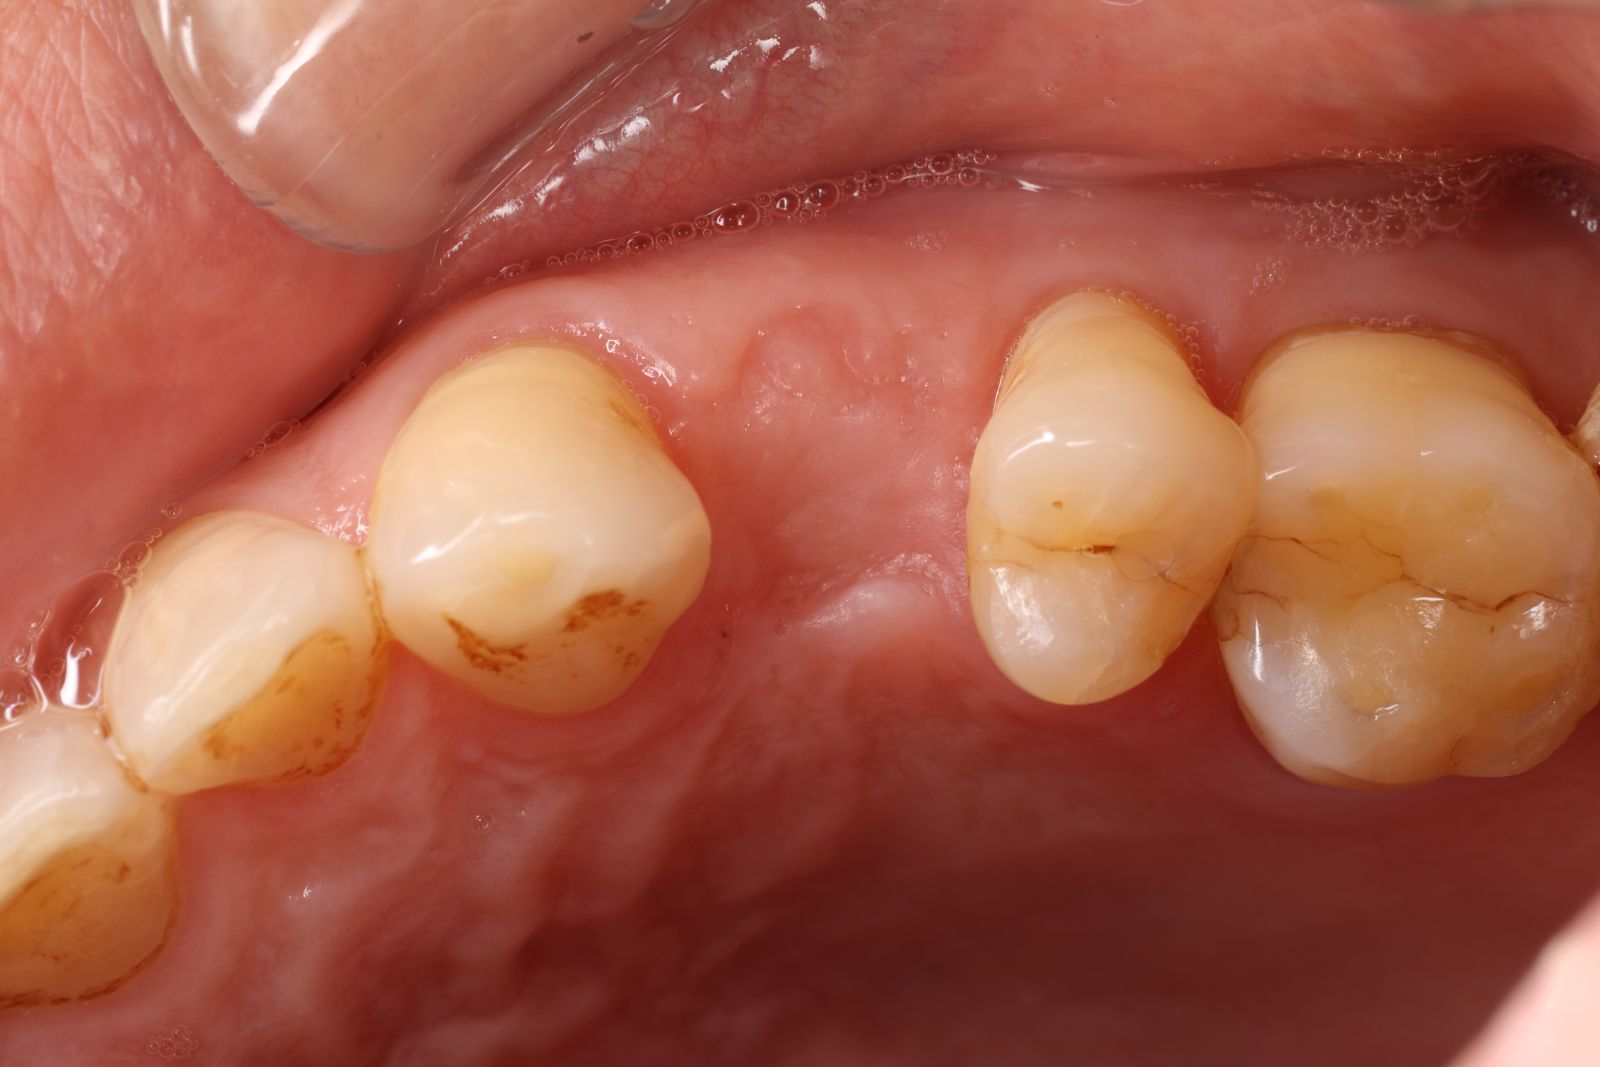

【 案 例 二】

- 手術過程,在植入植體前先用導板定位,確認植牙位置及角度。

- 手術中先使用導板定位,確認植牙角度及位置

- 藉由導板的定位,無須劃開傷口,精準的植入植體。

- 植入植體後不用劃開傷口無須縫合,鎖上癒合帽等待骨整合完成,過程輕鬆舒適。

- 3-4個用即可裝上全瓷牙冠恢復咬合功能